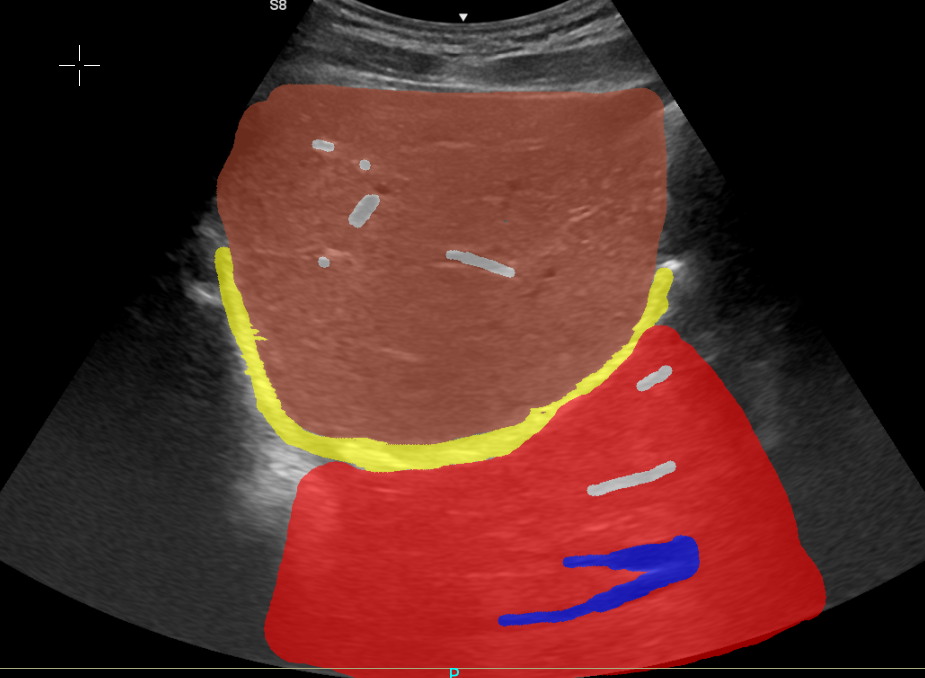

Artefacto en espejo en región hepática con etiquetas anatómicas

Visor interactivo del artefacto en espejo hepático

Cuando el diafragma actúa como superficie reflectante, las estructuras cercanas aparecen en su posición real y también como una imagen "espejo" al otro lado. Este fenómeno es especialmente común en:

• Interfaz hígado-diafragma

• Interfaz pulmón-diafragma

• Estructuras altamente reflectantes